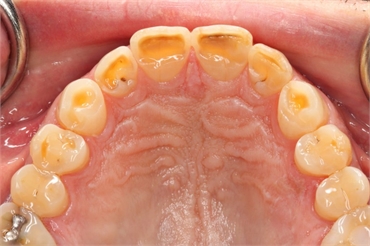

Sometimes, the surface of your teeth might appear worn out. This worn out appearance resembles a plane polished tooth surface, whose edges may be sharp or rounded. The worn out surface can be any tooth surface. It might be the surface that helps in chewing, the surface that corresponds to the cheeks or the surface in proximity to the tongue.

Attrition is physiological, abrasion is mechanical whereas erosion is chemical. It occurs when the tooth "corrodes" by the consumption of various acids from certain foods and drinks. It is most commonly seen on the back surfaces of the upper front teeth and on the chewing surfaces of both upper and lower teeth. People with a tendency of gastrointestinal disorders which involves frequent vomitting, rumination, etc are likely to develop wear facets due to erosion.